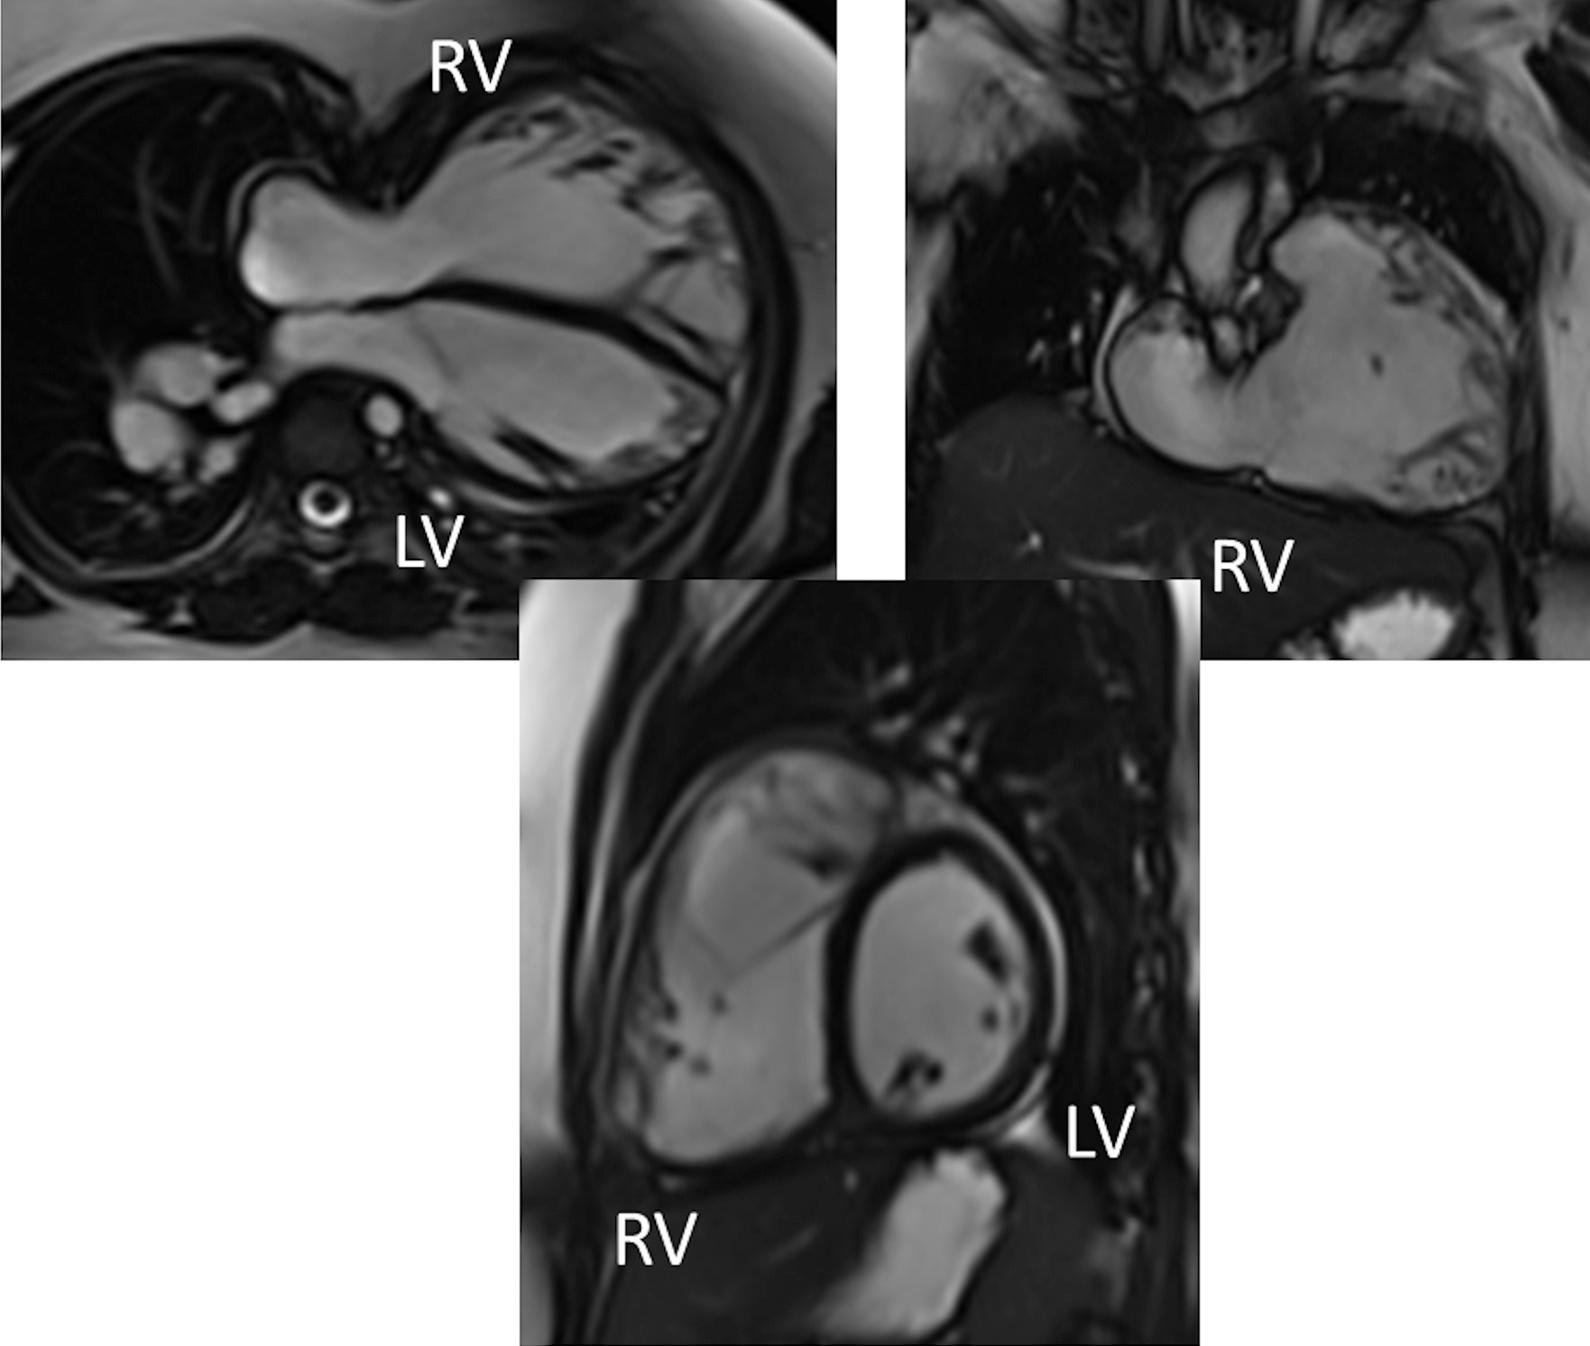

Cardiovascular magnetic resonance (CMR) has been utilized in the management and care of pediatric patients for nearly 40 years. It has evolved to become an invaluable tool in the assessment of the littlest of hearts for diagnosis, pre-interventional management and follow-up care. Although mentioned in a number of consensus and guidelines documents, an up-to-date, large, stand-alone guidance work for the use of CMR in pediatric congenital 36 and acquired 35 heart disease endorsed by numerous Societies involved in the care of these children is lacking. This guidelines document outlines the use of CMR in this patient population for a significant number of heart lesions in this age group and although admittedly, is not an exhaustive treatment, it does deal with an expansive list of many common clinical issues encountered in daily practice.

心血管磁共振(CMR)在儿科患者的管理和护理中已经应用了近 40 年。它已经发展成为评估最小的心脏的宝贵工具,用于诊断、介入前管理和随访。尽管在许多共识和指南文件中提到,但在儿科先天性心脏病和后天性心脏病领域,目前还缺乏一份由众多参与儿童护理的学会共同认可的、最新的、独立的、针对 CMR 使用的大型指南。本指南文件概述了 CMR 在该年龄段的许多心脏病变中的应用,尽管不能说是详尽的治疗方法,但它确实涉及了在日常实践中经常遇到的许多常见临床问题的广泛列表。